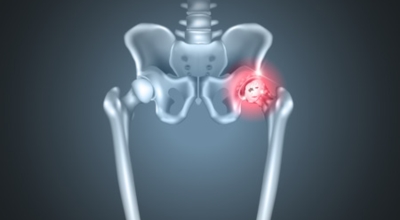

고관절염은 고관절에 나타나는 관절염을 말하며 고관절의 연골이 닳게 되면서 뼈와 뼈가 서로 부딪히며 통증을 일으키게 돼요. 고관절염 초기 증상으로는 사타구니 부위가 불편하게 느껴지며, 무리하면 통증이 발생할 수 있으며, 관절염 증상이 심해지면서 사타구니에서 느끼던 통증이 허벅지와 엉덩이 통증으로 이어지기도 하는데, 고관절염 통증 증상으로 초기에는 허리 통증이 나타나 허리 질환과 혼동하기 쉬우며 각별히 척추질환이 있는 사람은 고관절 통증과 마찬가지로 엉덩이, 다리 통증이 동반되기 때문에 훨씬 헷갈리는 경우가 많습니다.

이 증상은 퇴행성 고관절염에 의해 생기는 현상으로 보통은 중장년층에게 자주 일어나는 질병입니다. 이 질병은 관절과 관절 사이에 존재하는 연골이 닳아 없어지면 관절 내부와 주위에 염증과 통증을 동반합니다. 보통 골반 아래단에 뻐근한 증상을 일으키고 양반다리 자세를 할 때 통증이 심해져요.

더불어 계단을 오를 때 통증이 심해지고 오래 걷는것도 힘들어 져요. 원인은 노화로 인한 연골 마모, 과체중, 고관절 질환을 방치하는 경우 입니다. 치료방법은 적절한 운동과 소염제를 사용하기도 하며 심할경우 수술 치료가 시행 될 수 있어요.